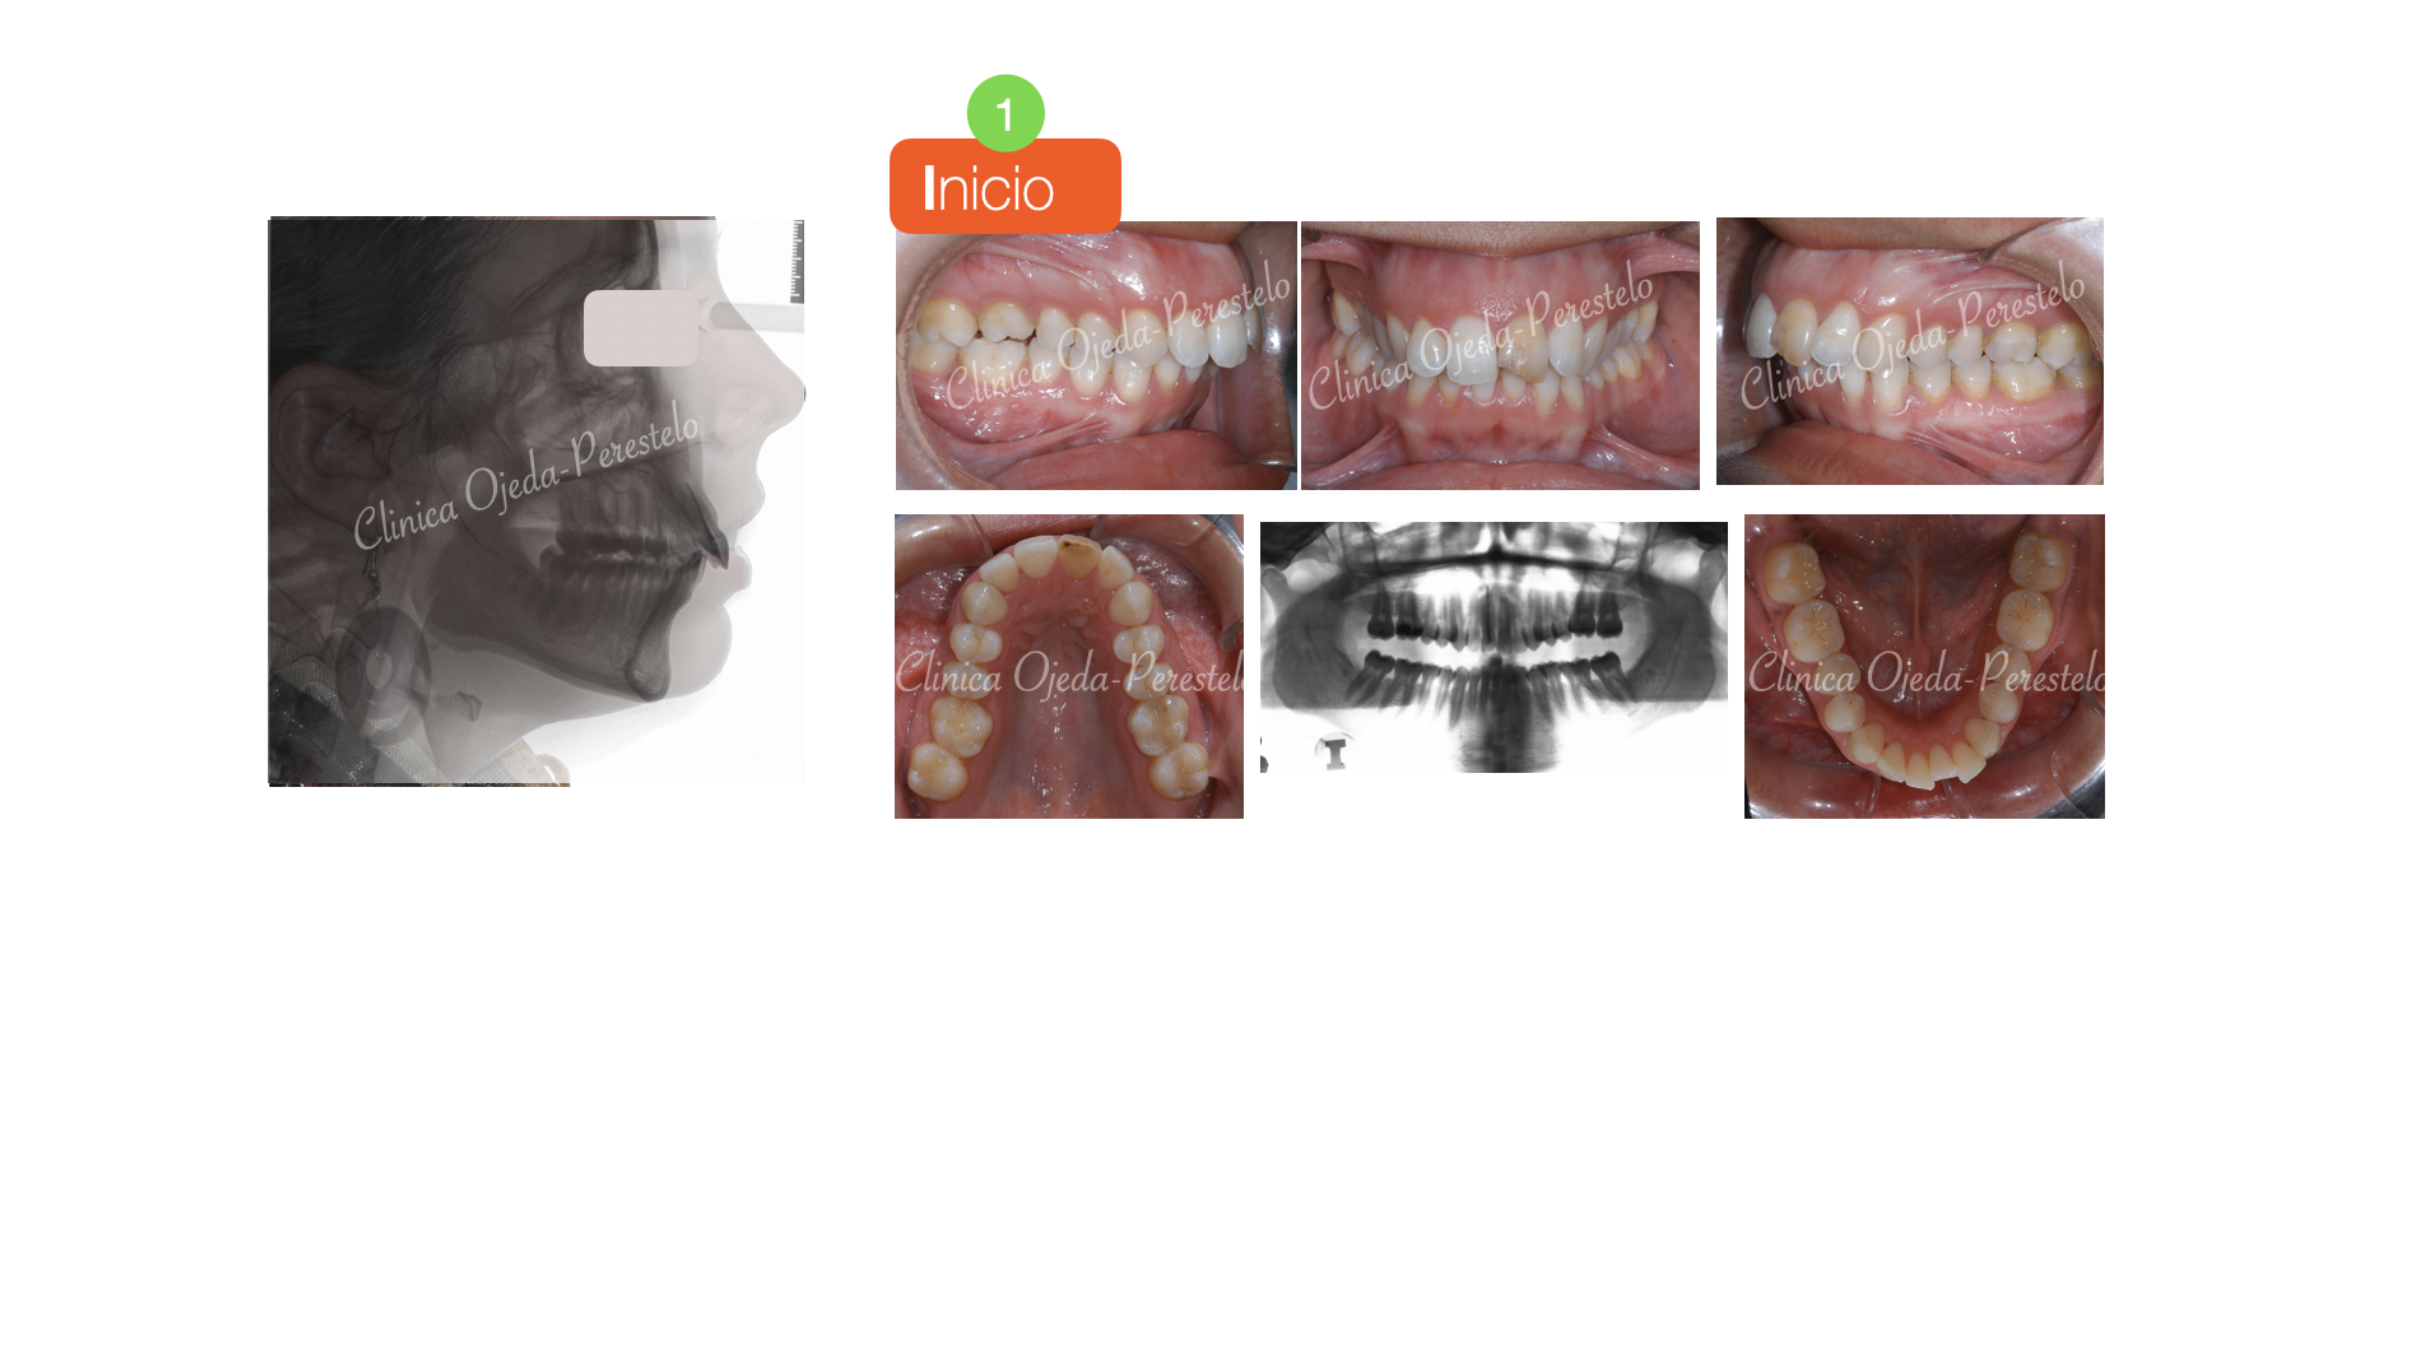

Sonrisa gingival (encías) con Resalte Aumentado

Paciente tratada con brackets de autoligado pasivo (Sistema Damon) donde hemos alineado, nivelado y expandido las arcadas. Hemos realizado las extracciones de los premolares superiores para disminuir el Resalte ya que la paciente no quería realizarse cirugía ortognática.

Quisieramos destacar cómo las extracciones de premolares no empeoran la amplitud de la sonrisa además de la mejora en la sonrisa gingival realizada con Microtornillos.